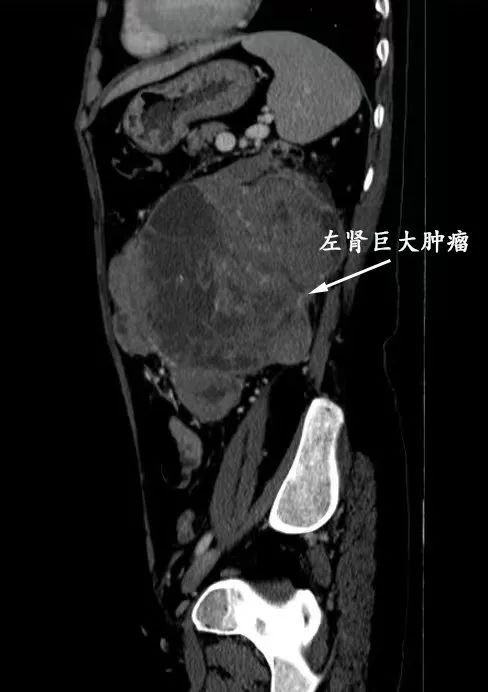

左为腹腔内肿物横断位CT片,右为矢状位CT片

邵远主任仔细阅片后,决定将患者收治入我院嘉定院区泌尿外科病房进行术前评估,同时在肾内科协助下规律透析治疗。我院检查发现,但女士肿物起源于左侧肾脏,体积达11*12.8*11.3cm,几乎填充整个左侧腹部(达T4期),推挤脾胃及同侧肠管。不仅如此,患者有两支左肾静脉,其主干及下腔静脉内均存在长段癌栓(将近Mayo Ⅲ级),一旦癌栓脱落,后果不堪设想。